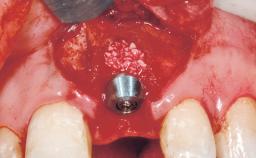

Early Placement of an Implant in a Maxillary Right Central Incisor Site

This 41-year-old female patient was referred to the clinic for the replacement of the right central incisor, since the tooth had developed a root fracture in the long axis that made extraction necessary. The healthy, non-smoking patient was first seen with the tooth still in place. A detailed Esthetic Risk Assessment was performed.The patient was worried about her dental esthetics and had high expectations for a successful treatment outcome from an esthetic point of view. The patient had a medium lip line that displayed parts of the gingiva in the anterior maxilla upon smile.

Type of Implants Two-Piece

Bone Augmentation Horizontal|Simultaneous

Augmentation Materials Autogenous chips|Xenogenous|Membrane

Bone Volume Deficient horizontally, allowing simultaneous augumentation